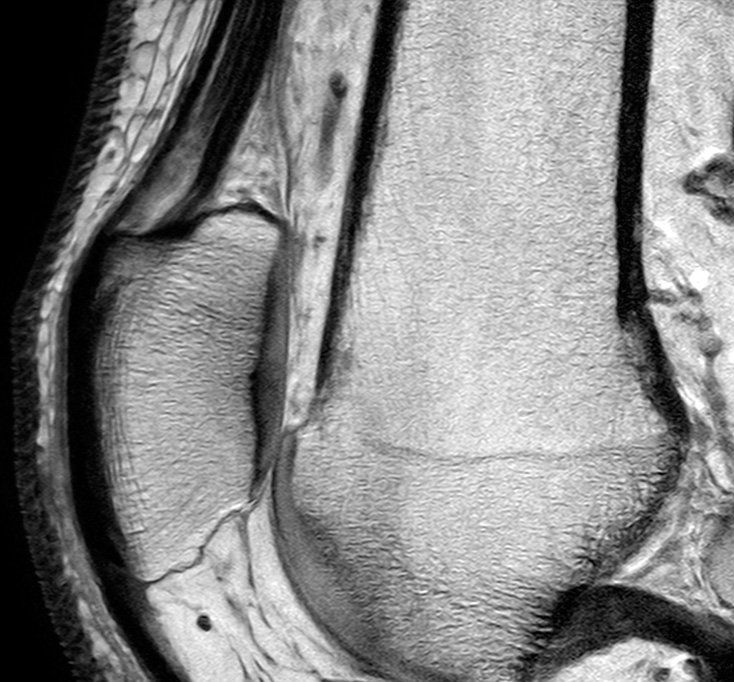

Knee MRI